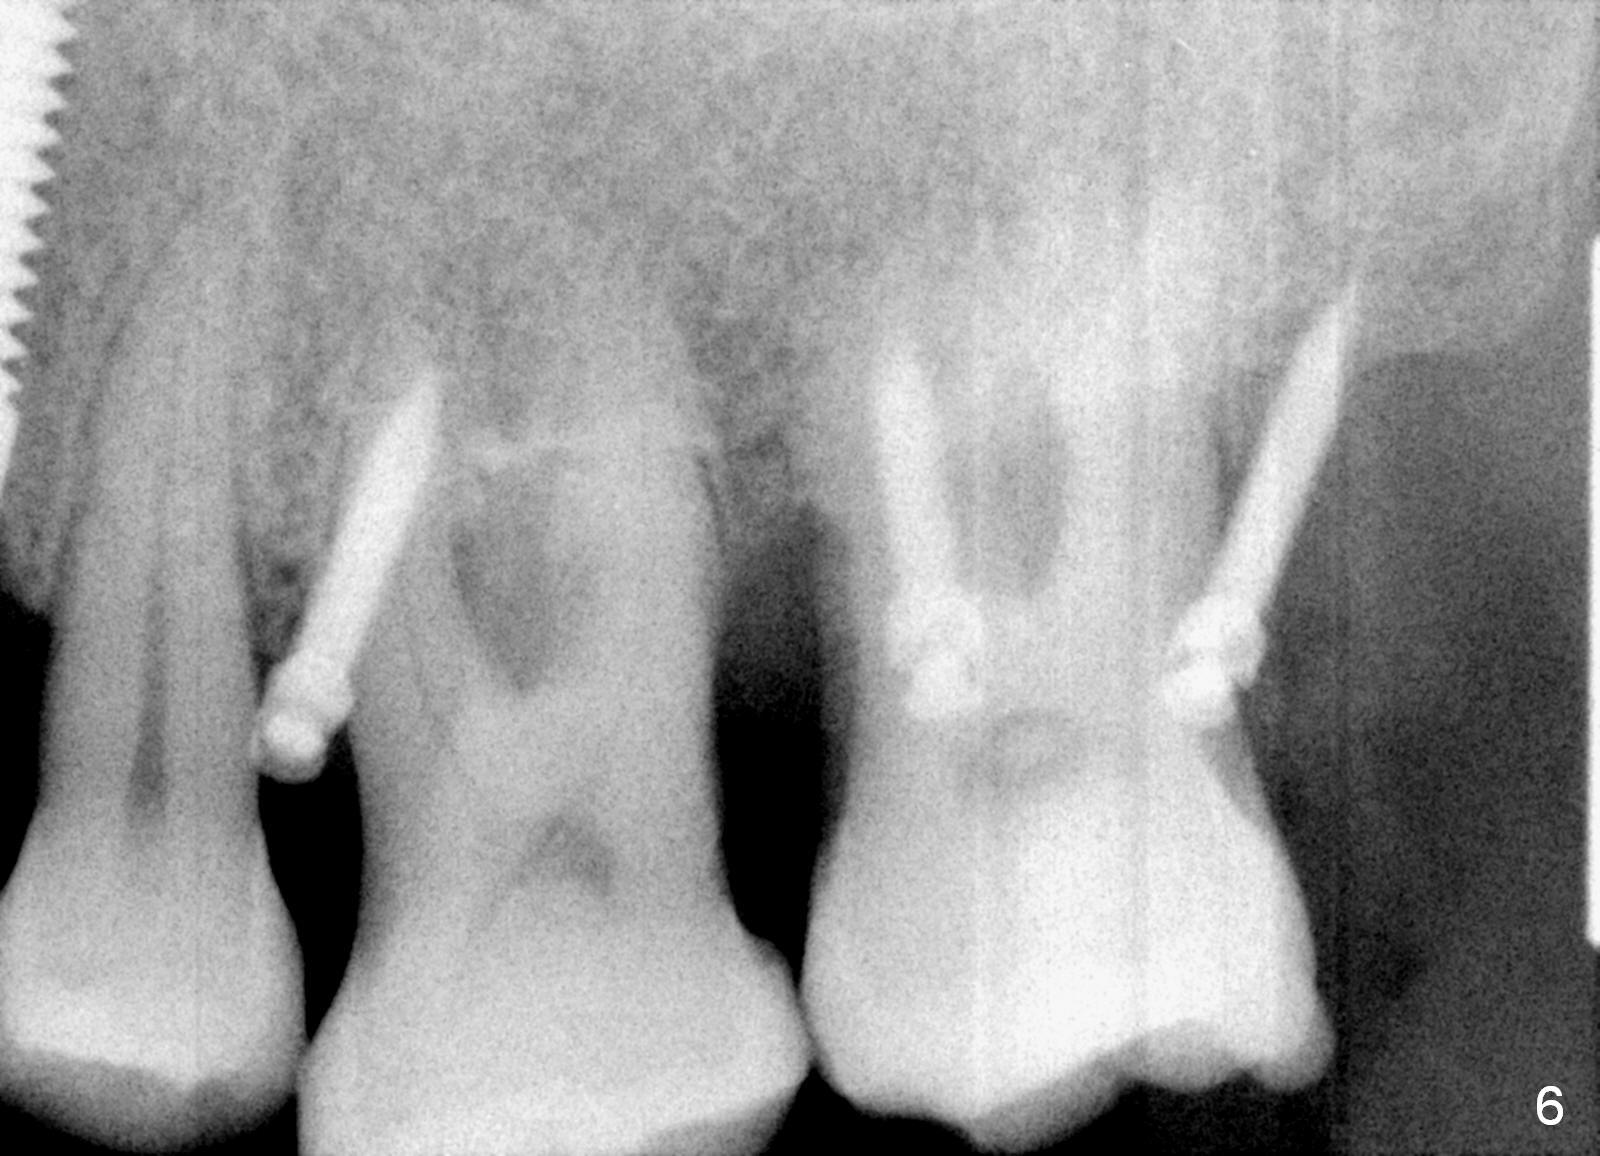

A 41-year-old man has chronic periodontits with bruxism. The teeth #14 and 15 are supraerupted (Fig.1 arrows) with furcal lesion (Fig.2 (CT) *). These 2 molars have guarded to poor prognosis. Due to insurance benefit limitation, we plan to save them temporarily with periodontal surgery so that bone loss would not get worse when the teeth are being intruded. After opposing implant placement (Fig.3), flaps are raised to remove calculus and granulation tissue (Fig.4, no bone graft). Twenty days later, three mini-implants are placed (Fig.5,6). The implant distopalatal to #15 is loose nearly 2 months postop (Fig.7 *) and retightened. The following month the same implant is placed higher for stability (Fig.8). The Intrusion takes <5.5 months (Fig.9,10).